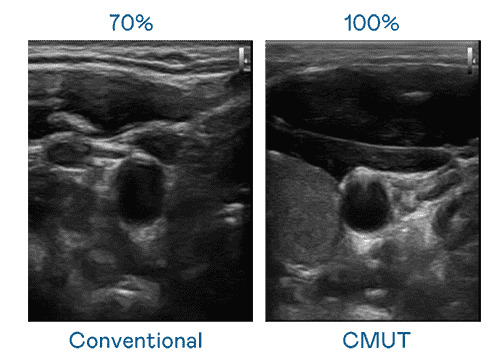

CMUT 技术是一种用电容式微机电元件来产生超音波讯号的技术。。。与传统 PZT 压电式技术相比,,,CMUT 频宽增加 30%,,,更宽频的超音波讯号让影像解析度大幅提升,,是实现高影像品质医疗超音波扫描、、、促进精准医疗发展的关键技术。。。

大频宽带来超清晰影像

超音波影像的解析度高低,,首先取决于探头能发出的讯号频宽。。尊龙z6 CMUT 可提供高清晰的超音波讯号,,提供高频宽、、高灵敏度、、、、影像纹理细节更高的超音波影像,,,协助医护人员缩短影像判读时间及利用精准的医疗影像进行诊断。。。